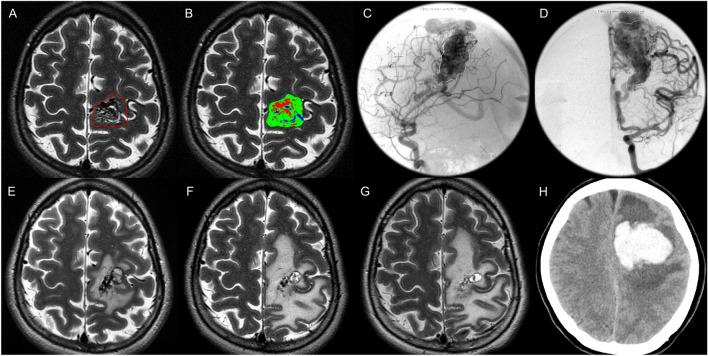

The aim of the study was to investigate whether morphology (i.e. compact/diffuse) of brain arteriovenous malformations (bAVMs) correlates with the incidence of hemorrhagic events in patients receiving Stereotactic Radiosurgery (SRS) for unruptured bAVMs. This retrospective study included 262 adult patients with unruptured bAVMs who underwent upfront SRS. Hemorrhagic events were defined as evidence of blood on CT or MRI. The morphology of bAVMs was evaluated using automated segmentation which calculated the proportion of vessel, brain tissue, and cerebrospinal fluid in bAVMs on T2-weighted MRI. Compactness index, defined as the ratio of vessel to brain tissue, categorized bAVMs into compact and diffuse types based on the optimal cutoff. Cox proportional hazard model was used to identify the independent factors for post-SRS hemorrhage. The median clinical follow-ups was 62.1 months. Post-SRS hemorrhage occurred in 13 (5.0%) patients and one of them had two bleeds, resulting in an annual bleeding rate of 0.8%. Multivariable analysis revealed bAVM morphology (compact versus diffuse), bAVM volume, and prescribed margin dose were significant predictors. The post-SRS hemorrhage rate increased with larger bAVM volume only among the diffuse nidi (1.7 versus 14.9 versus 30.6 hemorrhage per 1000 person-years in bAVM volume < 20 cm versus 20-40 cm versus > 40 cm; p = 0.022). The significantly higher post-SRS hemorrhage rate of Spetzler-Martin grade IV-V compared with grade I-III bAVMs (20.0 versus 3.3 hemorrhages per 1000 person-years; p = 0.001) mainly originated from the diffuse bAVMs rather than the compact subgroup (30.9 versus 4.8 hemorrhages per 1000 person-years; p = 0.035). Compact and smaller bAVMs, with higher prescribed margin dose harbor lower risks of post-SRS hemorrhage. The post-SRS hemorrhage rate exceeded 2.2% annually within the diffuse and large (> 40 cm) bAVMs and the diffuse Spetzler-Martin IV-V bAVMs. These findings may help guide patient selection of SRS for the unruptured bAVMs.

本研究旨在探讨接受立体定向放射外科 (SRS) 治疗的未破裂脑动静脉畸形 (bAVM) 患者,其 bAVM 的形态(致密型/弥漫型)是否与出血事件的发生相关。本回顾性研究纳入了 262 例接受初始 SRS 治疗的未破裂 bAVM 成年患者。出血事件定义为 CT 或 MRI 上有出血证据。bAVM 的形态使用自动分割进行评估,该方法计算 T2 加权 MRI 上 bAVM 中血管、脑组织和脑脊液的比例。致密指数定义为血管与脑组织的比值,根据最佳截断值将 bAVM 分为致密型和弥漫型。Cox 比例风险模型用于确定 SRS 后出血的独立因素。中位临床随访时间为 62.1 个月。SRS 后有 13 例(5.0%)患者发生出血,其中 1 例发生 2 次出血,年出血率为 0.8%。多变量分析显示,bAVM 形态(致密型与弥漫型)、bAVM 体积和预设边缘剂量是显著的预测因素。仅在弥漫性 nidi 中,随着 bAVM 体积的增大,SRS 后出血率增加(bAVM 体积 < 20 cm、20-40 cm 和 > 40 cm 时的每年出血率分别为 1.7、14.9 和 30.6 出血/1000 人年;p=0.022)。与 Spetzler-Martin 分级 I-III 相比,Spetzler-Martin 分级 IV-V 的 bAVM 的 SRS 后出血率显著更高(20.0 与 3.3 出血/1000 人年;p=0.001),主要来源于弥漫性 bAVM,而非致密型亚组(30.9 与 4.8 出血/1000 人年;p=0.035)。致密型和较小的 bAVM,以及较高的预设边缘剂量,其 SRS 后出血风险较低。弥漫性和较大 (> 40 cm) bAVM 以及弥漫性 Spetzler-Martin IV-V bAVM 的 SRS 后出血率每年超过 2.2%。这些发现可能有助于指导未破裂 bAVM 的 SRS 患者选择。